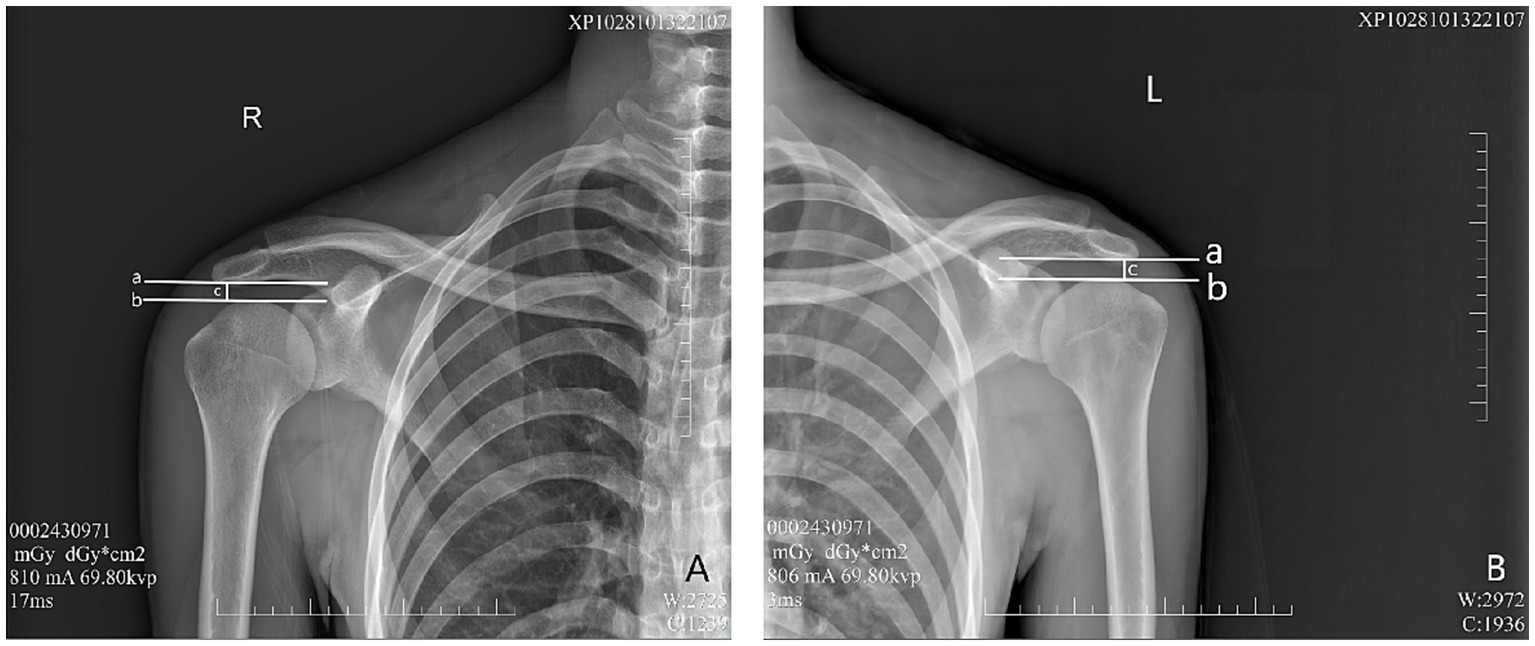

In the evaluation of AHD during radiographic procedures, the research included 28 healthy participants based on the informed consent of each participant. During the assessment via radiography (Simens Yiso, Fluorospot compact imaging systems, Germany) (Parameter settings: tube voltage 70 kV, automatic tube current, and small focal spot), participants were asked to maintain an upright position with their arms resting comfortably alongside their bodies and palms oriented towards their torso (Figures 1A,B). A vertical reference line was marked from the lowest point of the acromion, perpendicular to a horizontal line drawn from the top of the humeral head, which allowed for the measurement of the distance between the acromion and the humeral head (17) (Winning Health TView 6.1.0, Winning Health Technology Group Co., Ltd.) (Figures 2, 3). And the ratio of the bilateral distances was calculated (Left/Right). These procedures were performed by a single radiologist. It was made that the consistency of the results was evaluated for the distances from the healthy participant to the flat plane detector, measuring at 0 cm and 50 cm (Figures 1–3).

Figure 2

Evaluation of AHD distance from the healthy participant to the flat plane detector at 0 cm. a—A horizontal vertical line across the lowest point of the acromion. b—A horizontal line across the top of the humeral head. c—Distance between lines A and B, as well as AHD. (A) Right shoulder, (B) Left shoulder.